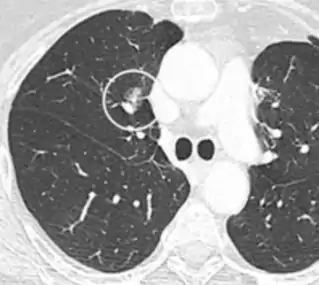

- Location: Upper lobe location is a risk factor for cancer, while a location close to a fissure or the pleura indicates a benign lymph node,[8] especially if having a triangular shape.[9]

- Margin morphology: a spiculated margin is a risk factor for cancer.[8] Benign causes tend to have a well defined border, whereas lobulated lesions or those with an irregular margin extending into the neighbouring tissue tend to be malignant.[10] In particular, spiculations are highly predictive of malignancy with a positive predictive value up to 90%.[9] Also, a "notch sign", which is an abrupt indentation of the nodule, increases the risk of cancer, but may also be found in granulomatous diseases.[9]